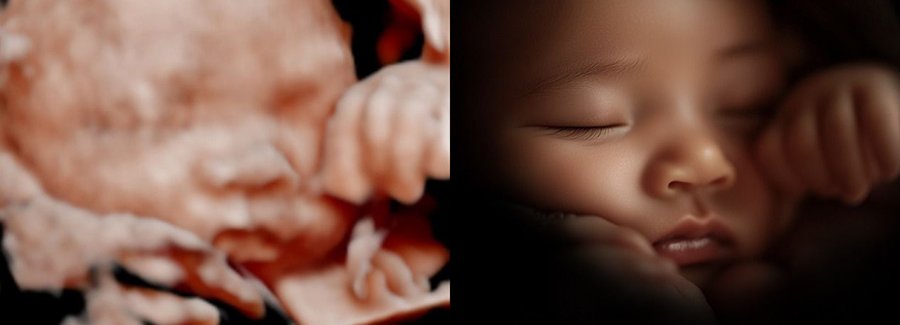

Often referred to as 5D, HD or FRV (fetal realistic view), 5D/HD is the newest development in pregnancy imaging. It captures and combines high definition volume data to create automated images with amazing color and clarity so you can see your baby as though you were looking from inside the womb.